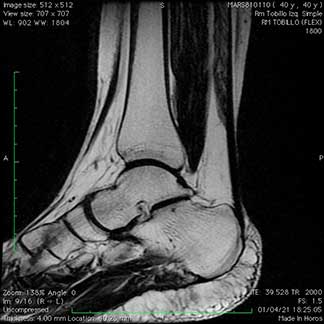

Resonancia magnética de tobillo de paciente con inestabilidad antero lateral